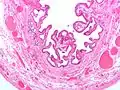

| Micrograph of cholesterolosis of the gallbladder, with an annotated foam cell. H&E stain. | |

The name strawberry gallbladder comes from the typically stippled appearance of the mucosal surface on gross examination, which resembles a strawberry. Cholesterolosis results from abnormal deposits of cholesterol esters in macrophages within the lamina propria (foam cells) and in mucosal epithelium. The gallbladder may be affected in a patchy localized form or in a diffuse form. The diffuse form macroscopically appears as a bright red mucosa with yellow mottling (due to lipid), hence the term strawberry gallbladder. It is not tied to cholelithiasis (gallstones) or cholecystitis (inflammation of the gallbladder).[2]